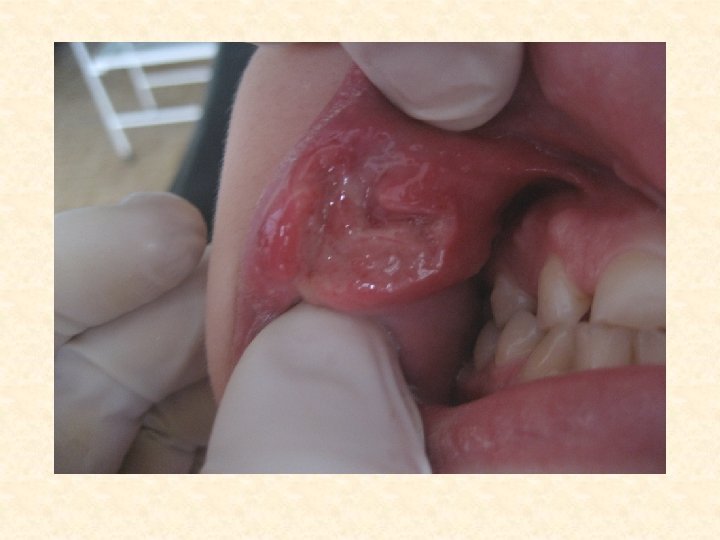

Элементом поражения при ХРАСе является или эрозия, или язва. Поверхностная эрозия представляющая собой дефект эпителия округлой формы, размером от 2 до 10 мм, покрытая фибринозным налетом, окруженная ярко красным ободком гиперемии получила название АФТА.

Фибринозная форма ХРАС • • • Чаще у женщин. Возраст начала первичной атаки – 10 30 лет. Частота рецидивов – от 1 2 атак в год, до нескольких рецидивов в течение месяца, вплоть до перманентного течения. Предвестники – чаще парестезия слизистой оболочки, иногда субфебрильная температура, локализованная лимфаденопатия, отек слизистой, чаще языка. Клиническое течение – одиночные или множественные изъязвления (афты), резко болезненные. Появлению могут предшествовать узелки, воспаление мелких слюнных желез. Количество элементов – от 1 до 100. В большинстве случаев 1 6 элементов. Размер – от 2 3 мм до 1 см. Локализация – слизистая оболочка полости рта, покрытая многослойным плоским неороговевающим эпителием. Течение – заживление происходит в течение 7 14 дней. Заживление происходит с образованием нежного рубца или без видимого рубцевания.

ХРАС, фибринозная форма.

Хронический рецидивирующий афтозный стоматит (ХРАС) . • Больной Н. , 22 года. • Клинический диагноз: ХРАС, фибринозная форма. Третий день после возникновения.